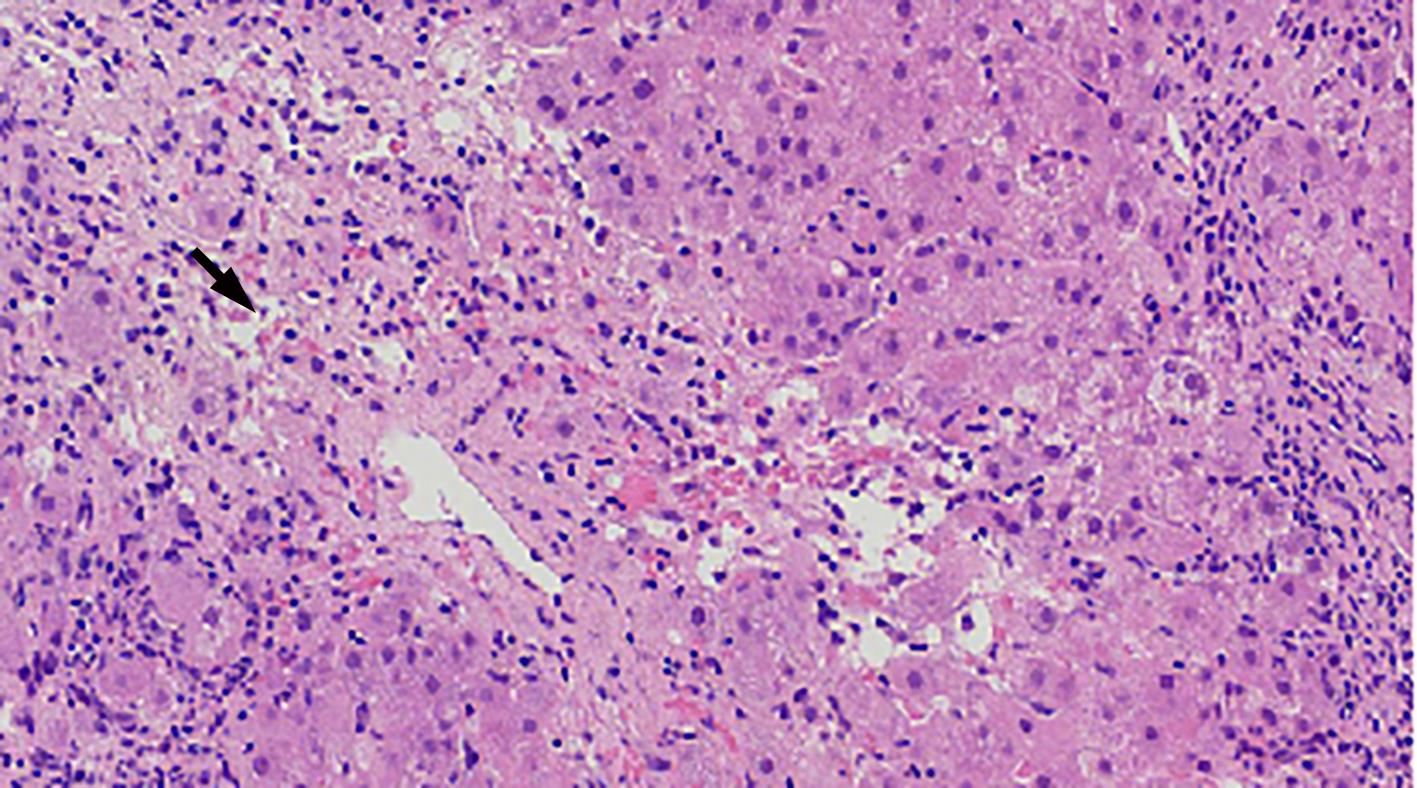

自身免疫性肝炎(AIH)是免疫介导的肝实质炎症性疾病,以高丙种球蛋白血症、自身抗体阳性和典型的肝组织学异常为特征。然而,AIH临床表现多样,缺乏特异性的血清学标志物,因此AIH的诊断困难,具有挑战性。虽然汇管区淋巴浆细胞浸润、界面性肝炎、淋巴细胞穿入现象和肝细胞玫瑰花结为AIH典型的组织学特征,但在AIH中尚可观察到其他的一些形态学改变,包括小叶中心性坏死、Kupffer细胞内透明小球等。所以没有一个单一的组织学特征可直接诊断AIH,需结合临床和实验室检查,并排除其他原因引起的肝脏疾病,方可做出正确的诊断。本文总结了AIH的组织学特征、不同的病理组织学谱、常见的临床问题、主要的鉴别诊断和最新进展。

Abstract:Autoimmune hepatitis (AIH) is an immune-mediated inflammatory disease of the liver parenchyma, which is characterized by hypergammaglobulinemia, the presence of autoantibodies, and typical abnormalities in liver histology; however, the diverse clinical manifestations of AIH and the lack of specific serological markers have brought difficulties and challenges in the diagnosis of AIH. Although portal lymphoplasmacytic infiltration, interface hepatitis, lymphocyte emperipolesis, and hepatocyte rosettes are the typical histological features of AIH, many other histological features can also be observed in AIH, including centrilobular necrosis and Kupffer cell hyaline globules. Therefore, no single histological feature can be used for the diagnosis of AIH, and a confirmed diagnosis should be made with reference to clinical and laboratory examinations, with the exclusion of liver diseases due to other causes. This article summarizes the histological features of AIH, different histopathological spectrum, common clinical issues, differential diagnosis, and recent advances.